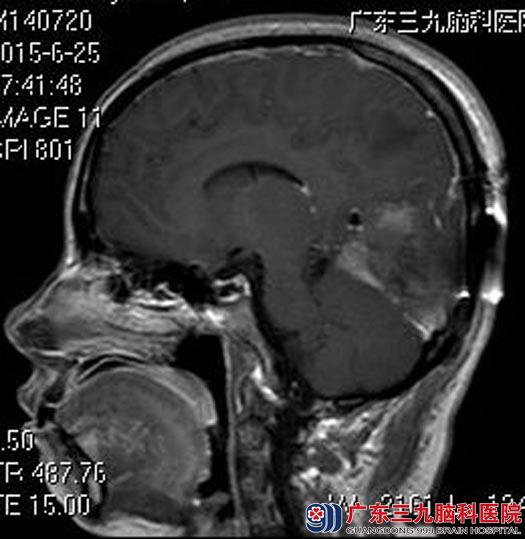

鲁明主任主刀在全麻下行右侧枕部镰旁脑膜瘤切除术,显微镜下见肿瘤呈灰白色、质韧、血供丰富,予以全切。手术后她恢复得很好,没有出现术后并发症及功能障碍。肿瘤顺利地切除了,陈女士的心理病也好了,术前那么多的担心都是多余的。术后病理结果:脑膜瘤(WHO I级)。

手术后